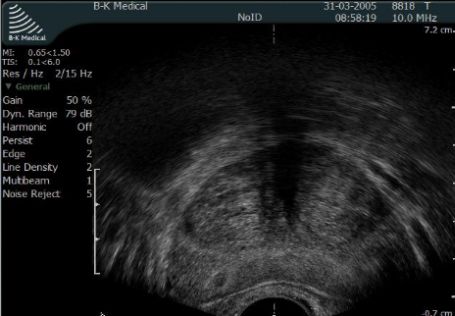

Badanie transrektalne gruczołu krokowego (TRUS)

Przezodbytnicza ultrasonografia gruczołu krokowego pozwala na precyzyją ocenę gruczołu krokowego oraz ocenę struktur bezpośrednio z nim sąsiadujących. Badanie wykonywane jest w pozycji leżącej na lewym boku i nie jest konieczne dobre wypełnienie pęcherza moczowego. Niewielka ilość moczu w pęcherzu poprawia jakość oceny sąsiadujących z prostatą struktur. Część lekarzy wymaga wykonania lewatywy bezpośrednio przed badaniem. W aptekach dostępne są gotowe preparaty np. Rectanal lub ENEMA.

Fot. Przekrój poprzeczny gruczołu krokowego widziany w transrektalnym USG.

Po ułożeniu pacjenta lekarz wprowadza do odbytnicy specjalną głowicę ultrasonograficzną - głowica transrektalna. Badanie jest dobrze tolerowane przez pacjentów i nie wymaga znieczulenia innego niż miejscowe żelem lignociainowym.